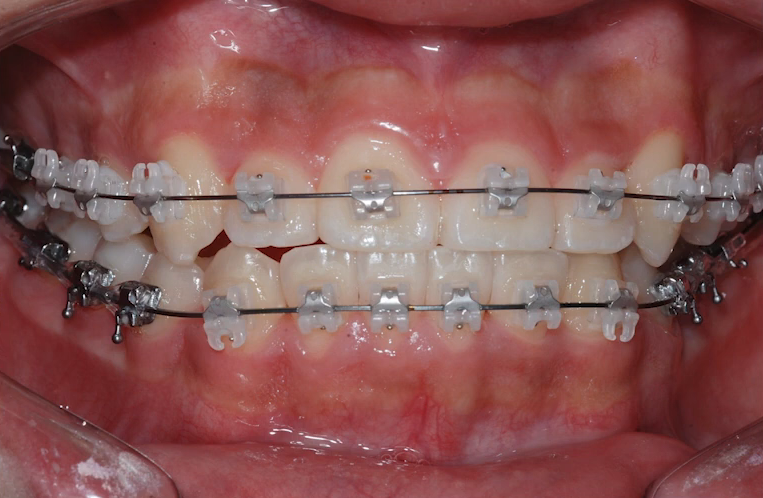

악궁확장 장치로 위, 아래 아치를 넓혀 자연스럽게 치아 사이를 벌려주고

그런 이후에 교정 장치를 부착해서 치아 배열을 고르게 해줬습니다.

덧니가 꽤 심했지만 확장을 통해 충분히 공간을 만든 후,

비발치로 교정을 끝낸 사례죠.

*치료 기간: 2022.03~2023.9